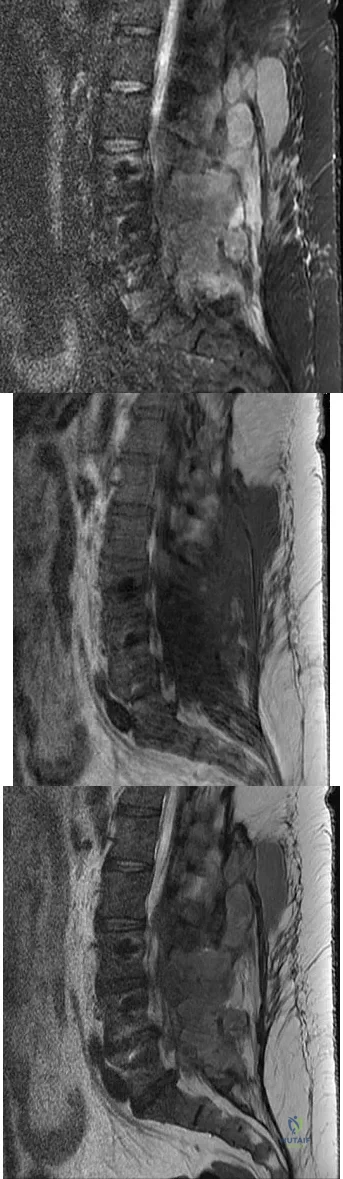

A 42-year-old woman underwent an instrumented posterior spinal fusion at L3-S1 with transforaminal lumbar interbody fusion. She had an excellent clinical result with complete resolution of leg pain. Three months later she now reports increasing back pain and weakness in her legs. Examination reveals weakness in the quadriceps and tibialis anterior. Radiographs show no interval changes in the position of the hardware. MRI scans are shown in Figures 2a through 2c. What is the next most appropriate step in management?

Explanation